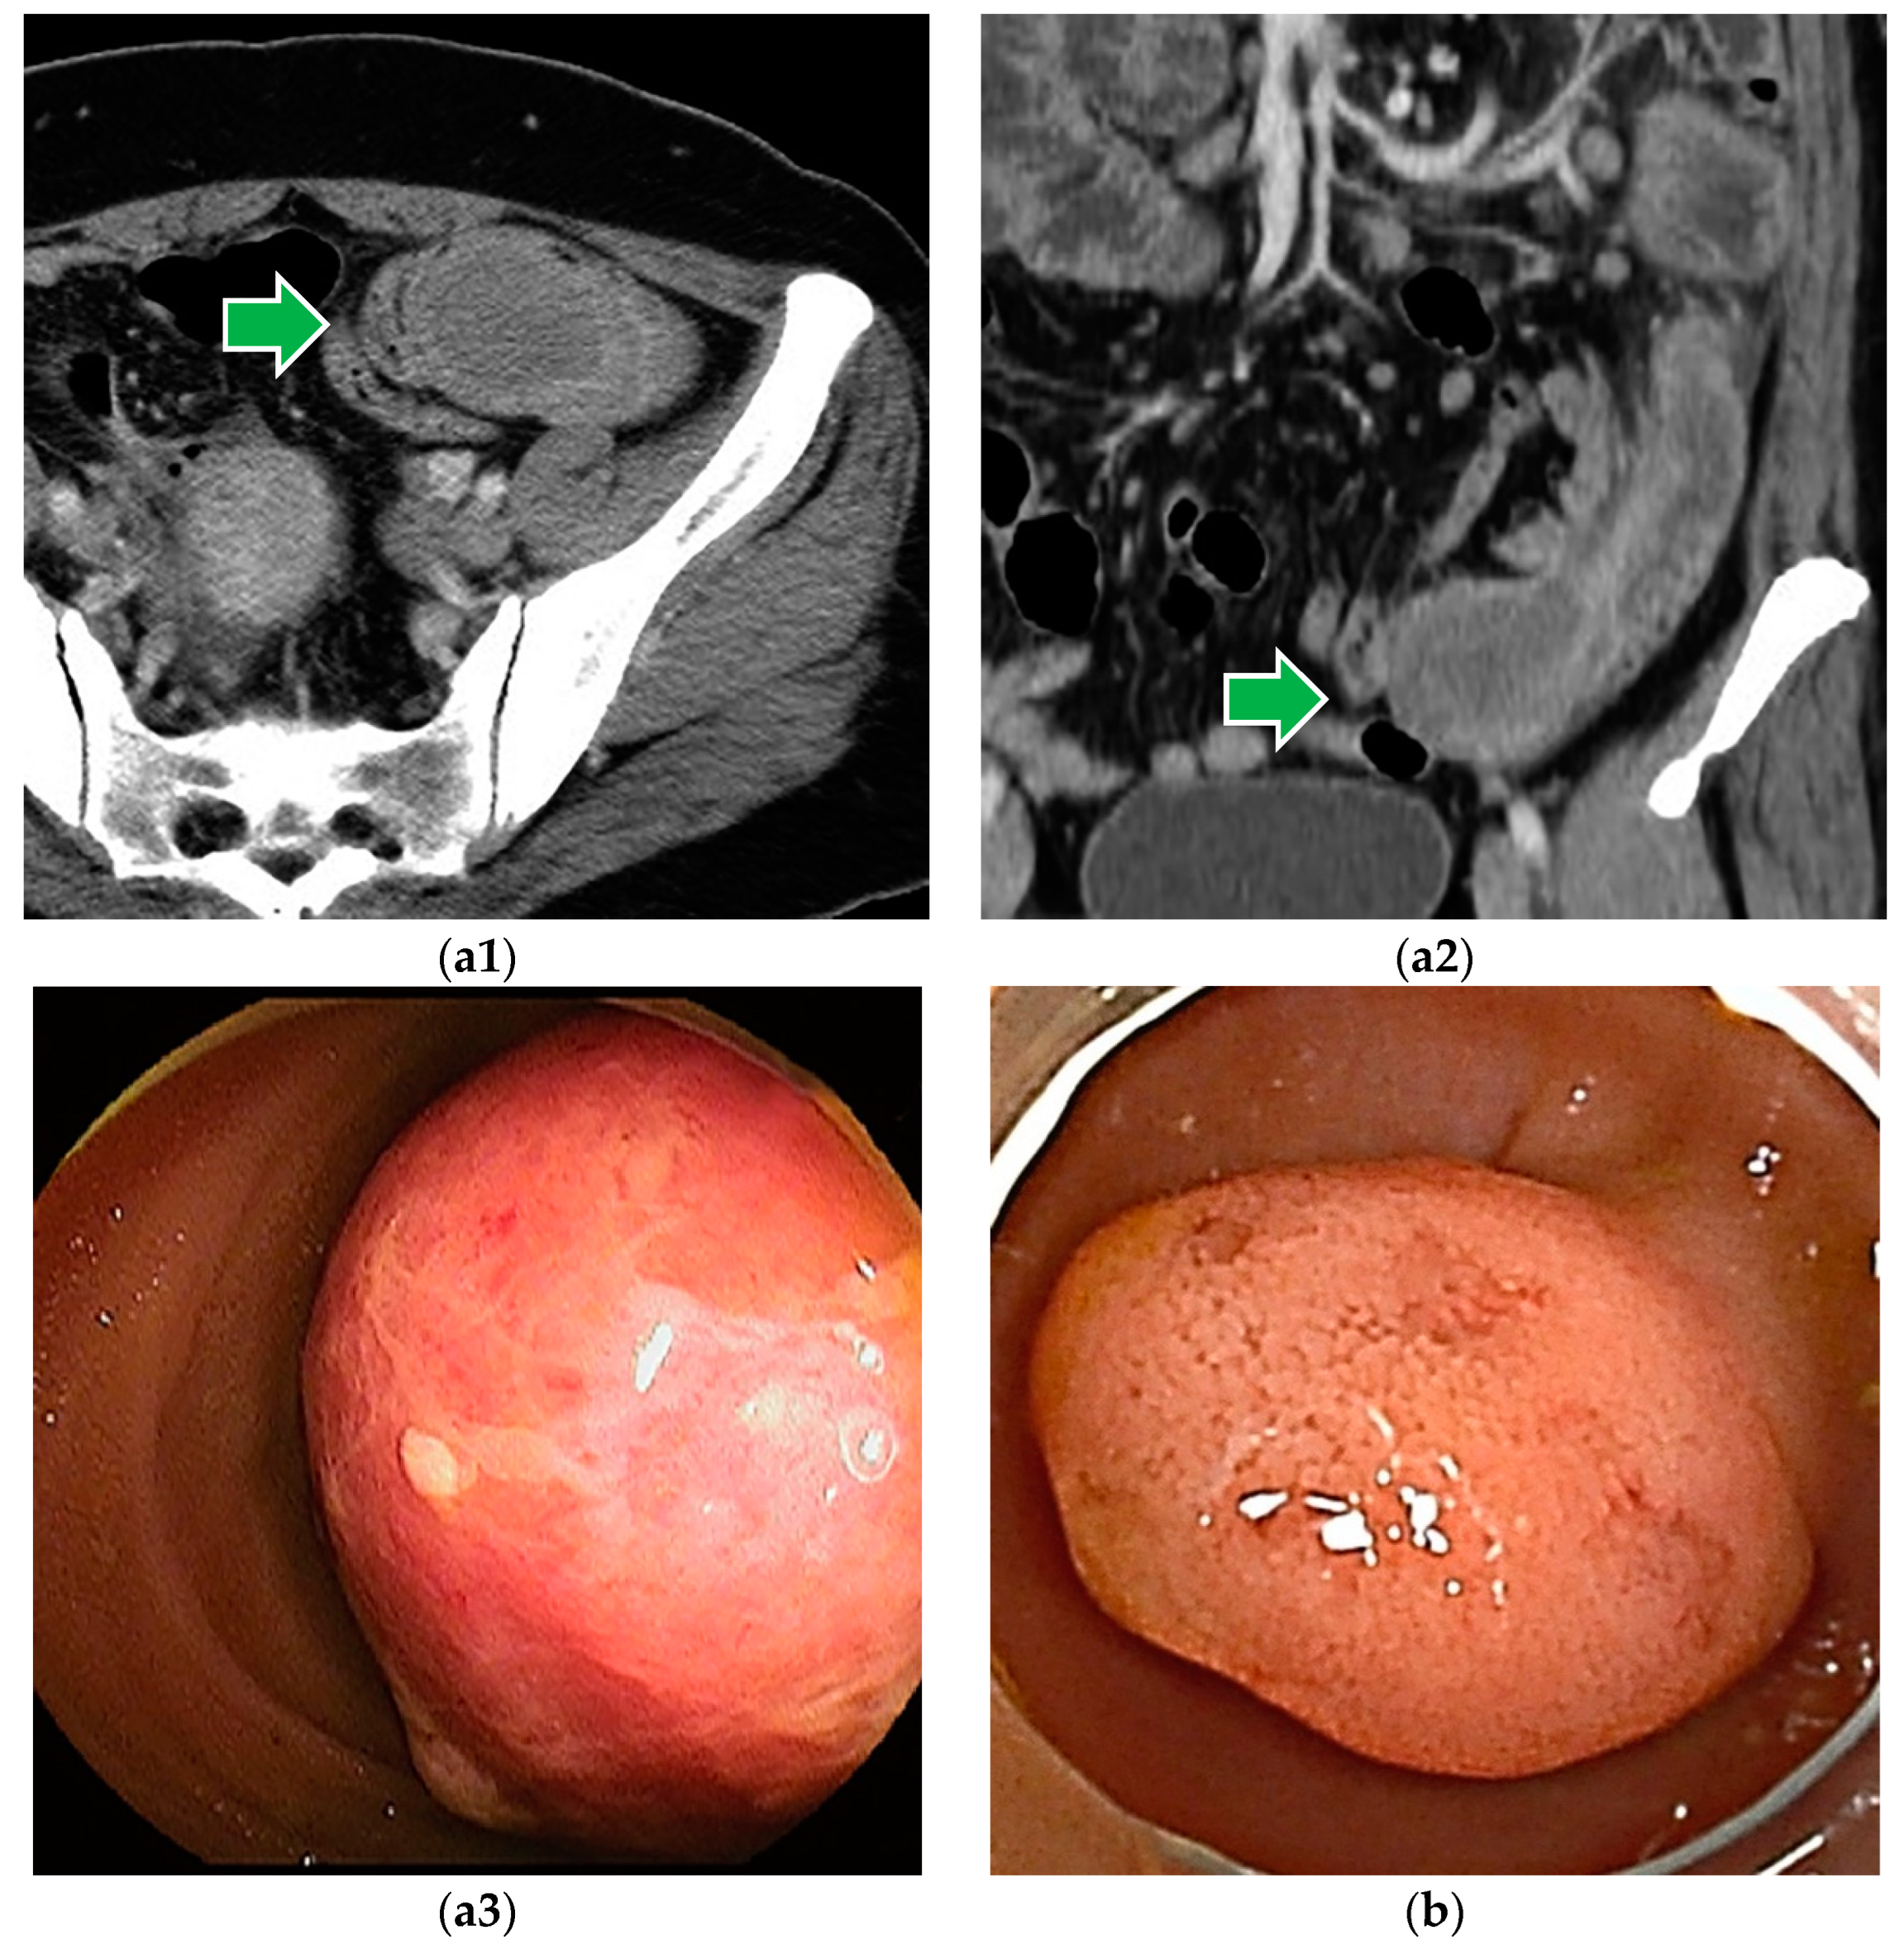

6.7. Peutz–Jeghers Syndrome

6.8. Familial Adenomatous Polyposis